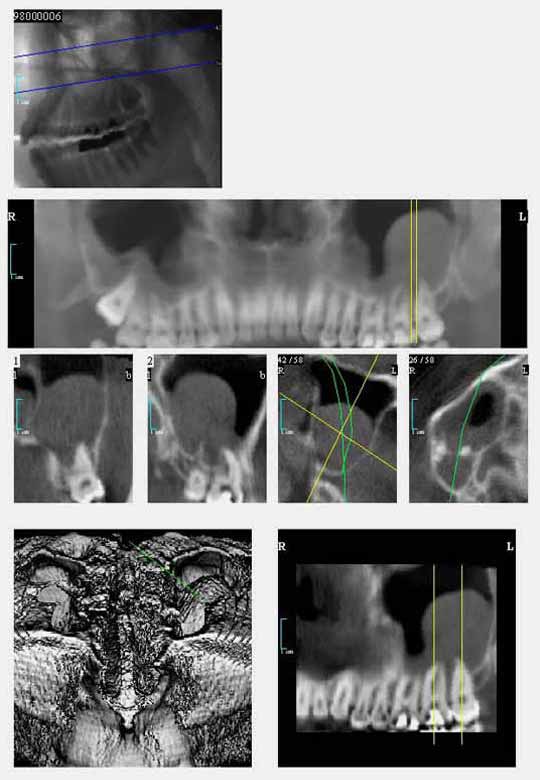

Der digitale Volumentomograph eröffnet für die Zahnheilkunde neue diagnostische Möglichkeiten. Wir setzen hier ein Gerät der Fa. Morita ein, das es ermöglicht auch kleine Aufnahmefelder (4*4 cm) zu tomographieren. Damit ist eine erhebliche Reduktion der Strahlenbelastung verbunden gegenüber Geräten, die nur große Aufnahmefelder untersuchen können. Wir nutzen diese Diagnostik für die Darstellung krankhafter Prozesse im Kiefer-Gesichtsbereich und für die Implantatplanung. Selbst für die Diagnostik vor Weisheitszahnentfernung kann eine solche Aufnahme sinnvoll sein, z.B. wenn die Gefahr einer besonderen Nervnähe besteht oder im Ramen einer Wurzelbehandlung wenn die Anatomie sich nicht durch zweidimensionale Aufnamen klären lässt.

Hier verläuft der Nervkanal direkt durch den Weisheitszahn. Dieser Befund kann nur durch die zweite Ebene gesichert werden. Das DVT erlaubt eine sichere Diagnostik und hilft, sicher zu entscheiden.